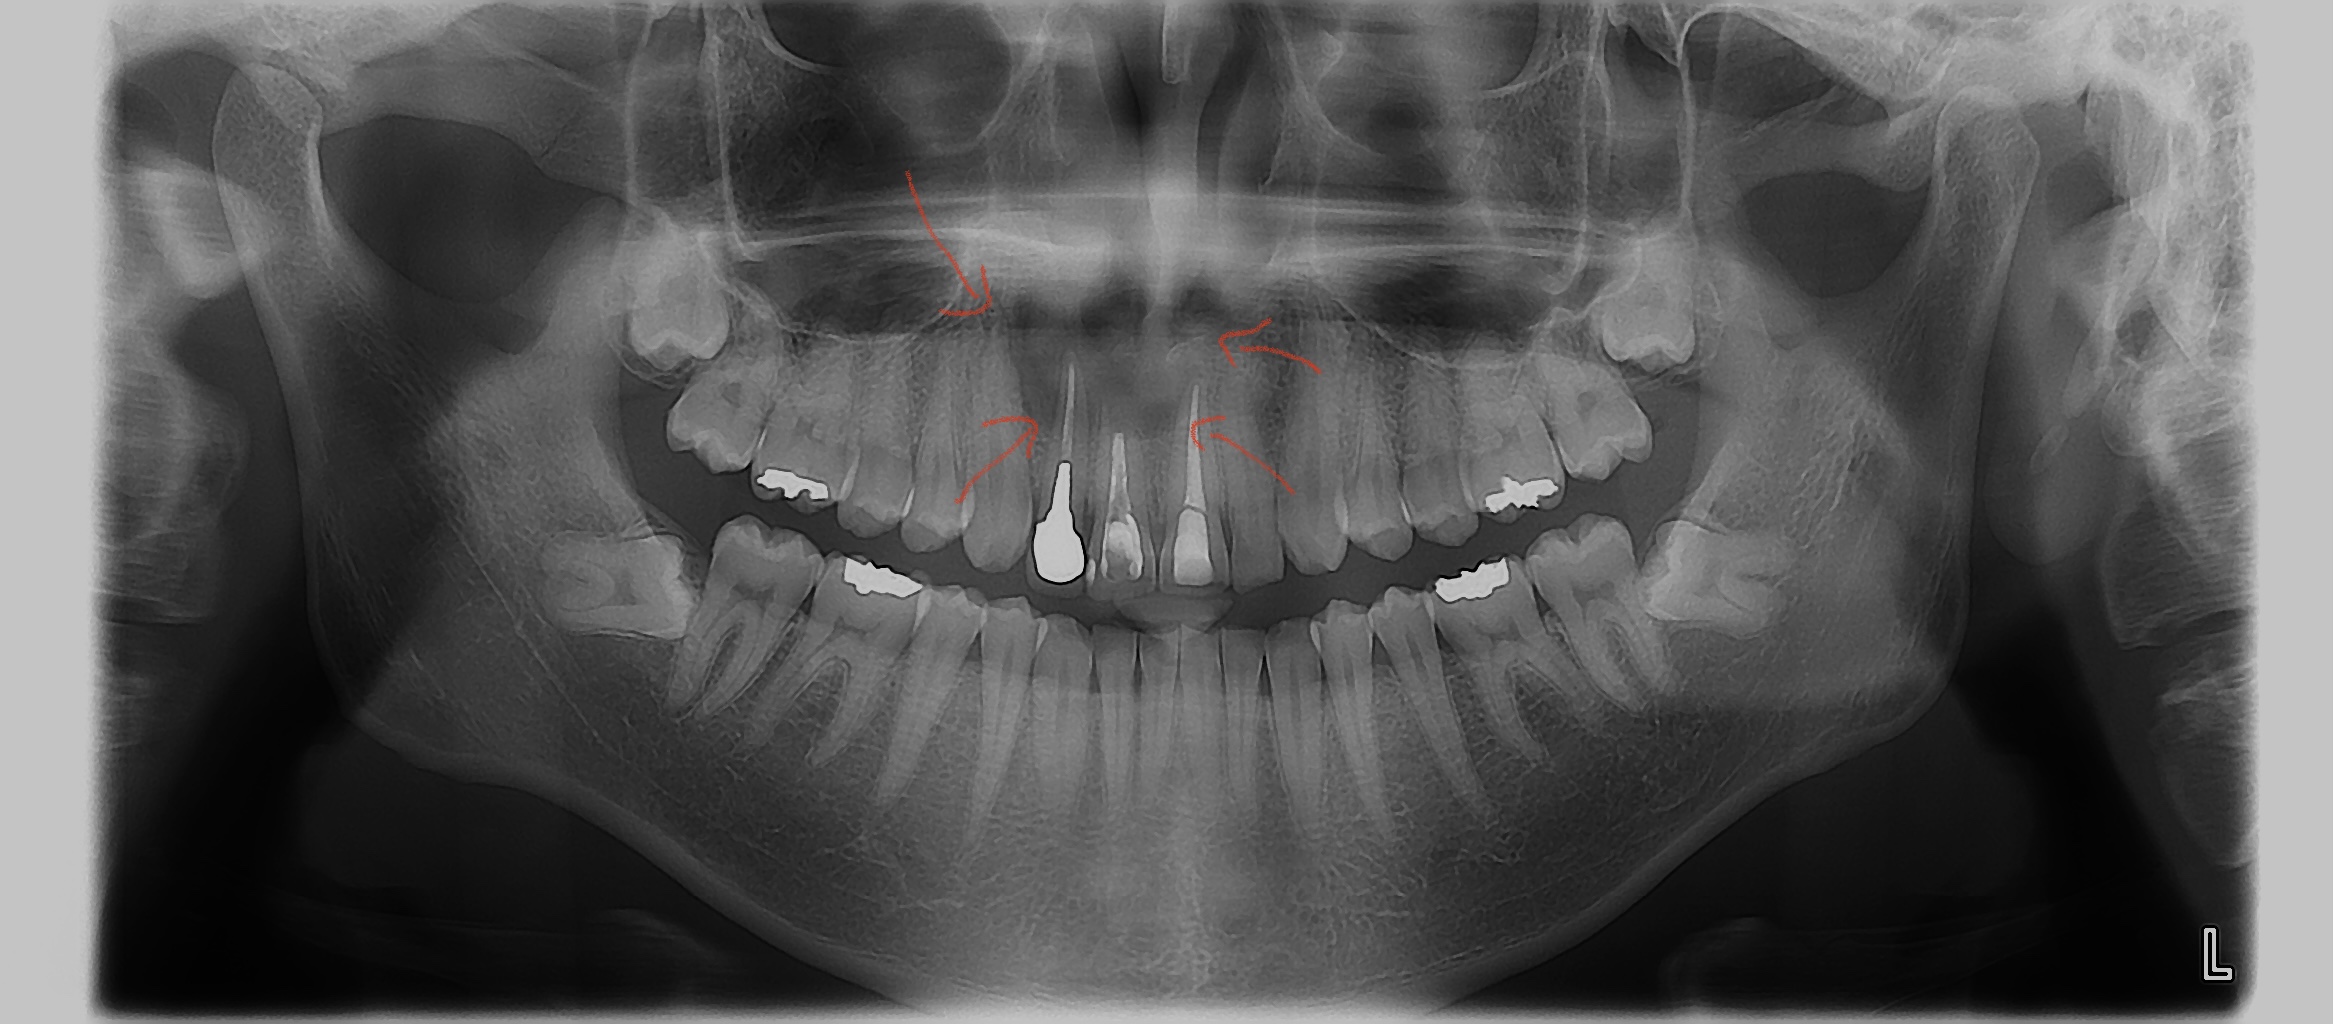

歯の根っこの先に炎症(膿が出ることもあります)が起こると赤矢印で囲まれた様にレントゲンで黒くなります。これが大きくなると嚢胞と呼ばれる袋状の出来物になります。こうなると、従来の根管治療だけでは治せない場合もあるので、外科的な治療が必要になる事があります。

この方の場合はマイクロスコープを用いて根管治療(一般的な神経の治療)+歯根端切除術(根っこの先を外科的に切除術)を行い治療をしました❗️

約1年経過しましたが、無事治ってきました✨患者さんは、抜歯してインプラントも覚悟して、他院からご紹介をして頂きましたが、ご自身の歯を残せて大変喜んでいました

治療前